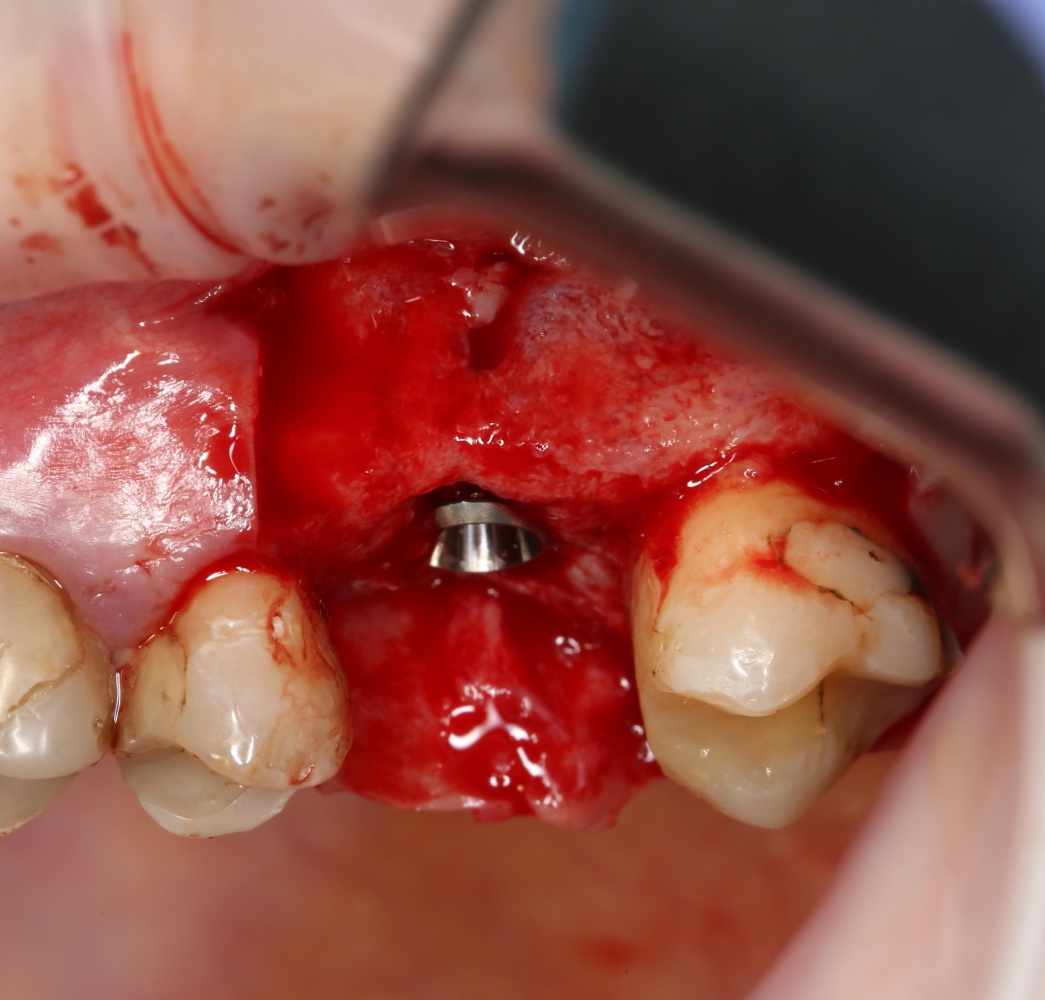

Установка имплантатов.

Напомню, что для этой работы я выбрал субкрестальные имплантаты Ankylos C/X. Они прекрасно сочетаются с любым методом остеопластики.

Я не планирую установку супраструктур или коронок, поэтому на уровень первичной стабильности можно положить болт. Даже наоборот — чем меньше крутящий момент при установке, тем лучше. Для имплантатов Ankylos и подобных им, это особенно важно. В общем, момент силы при установке — не более 10-15 Нсм.

Ремарка: имплантаты с предустановленными имплантодержателями хороши тем, что с ними легко контролировать позиционирование имплантатов. В случае с Ankylos С/Х - еще и крутящий момент. Имплантодержатель должен отсоединяться от имплантата с легким щелчком. Если его клинит, и тебе приходится прикладывать для этого усилия, то ты, однозначно, превысил момент силы во время установки имплантата. Следовательно, жди проблем.

Глянем на то, что получилось:

Осталось адаптировать костный блок (убрать острые края), проверить его фиксацию и, при необходимости, добавить винты. Десятисекундное дело.